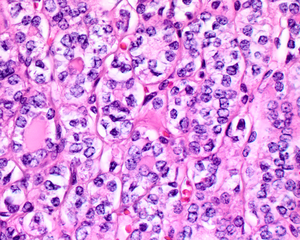

يُظهر ورم NIFTP سمات نووية محددة لسرطان الغدة الدرقية الحليمي.

السمات النووية لسرطان الغدة الدرقية الحليمي ، ولكن داخل ورم مغلف: NIFTP

4) يجب أن يتمتع بالسمات النووية المميزة لسرطان الغدة الدرقية الحليمي ، على الرغم من أنه في بعض الأحيان تكون السمات غير منتظمة في التوزيع دون أن يظهر الورم هذه السمات. يمكن تقسيم الميزات النووية إلى ثلاث فئات رئيسية:

• الحجم والشكل النوويان : التوسيع النووي ، والاستطالة النووية ، والتداخل والازدحام النووي. يعد فقدان القطبية النووية ، مع وجود نوى في المنطقة التجويف أو الوسطى أو القاعدية للخلايا اكتشافًا مفيدًا أيضًا.

• الانحرافات في الأغشية النووية : ملامح نووية غير منتظمة ، أخاديد وطيات نووية ، "عضات الفئران" أو تكوينات نصفية هلالية ، ووجود مشتملات هيولية داخل النواة.

• خصائص الكروماتين النووي: تنقية الكروماتين النووي ، غالبًا مع التكثيف أو التهامش على طول الأغشية النووية ، مما ينتج عنه هوامش نووية بارزة ، أو نوى زجاجية ، أو كروماتين نووي ناعم ، وحتى غباري.